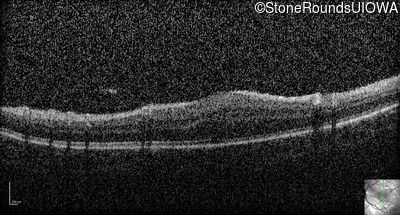

Optical Coherence Tomography - Left - 20/80

Exemplar / OCT Stack